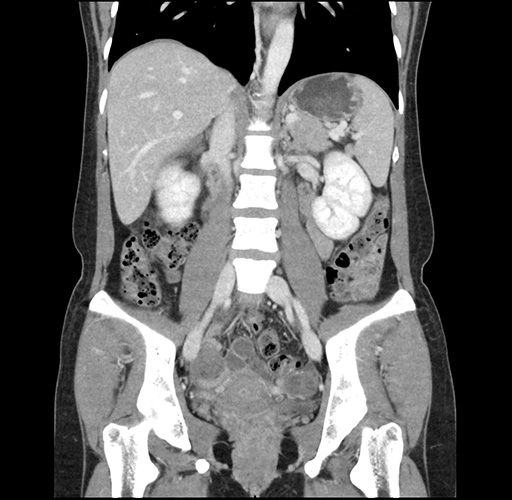

Left lateral sectionectomy [case 12]

Imaging Analysis

Look through the patient's CT scan to identify any areas of concern for the necessary procedure.

Based on your CT findings, which issue(s) would give reason for "planned slowing down moment(s)" in this case?

Considering a standard left lateral sectionectomy procedure, what step(s) of the operation would you do differently in this case ?